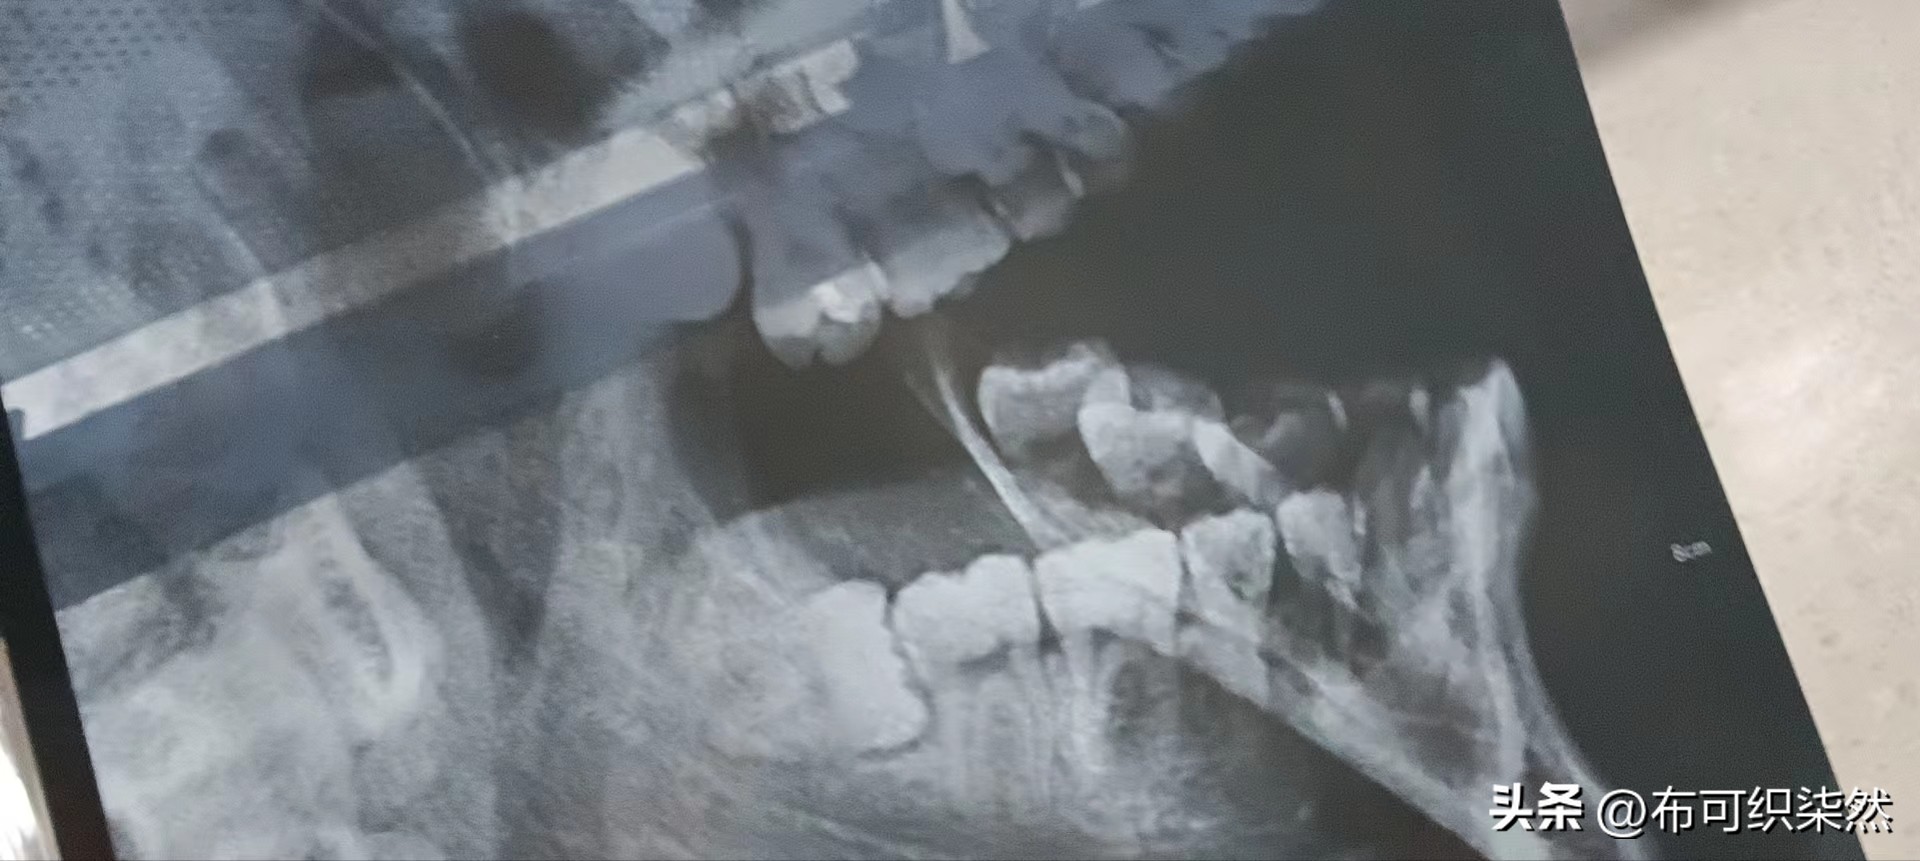

好久没去过大医院了,才发现挂号费已经到7块钱了,挂好号看完医生,拍完片子,医生告诉我长了个“三角齿”(阻生智齿),两个小时后,就准备拔牙了。

1)阻生智齿:横着长的智齿,歪着长的智齿,这类智齿往往会顶到前面的牙。

简单的说:只要是歪的智齿,不管疼不疼,看见了一律拔除,没有任何商量余地